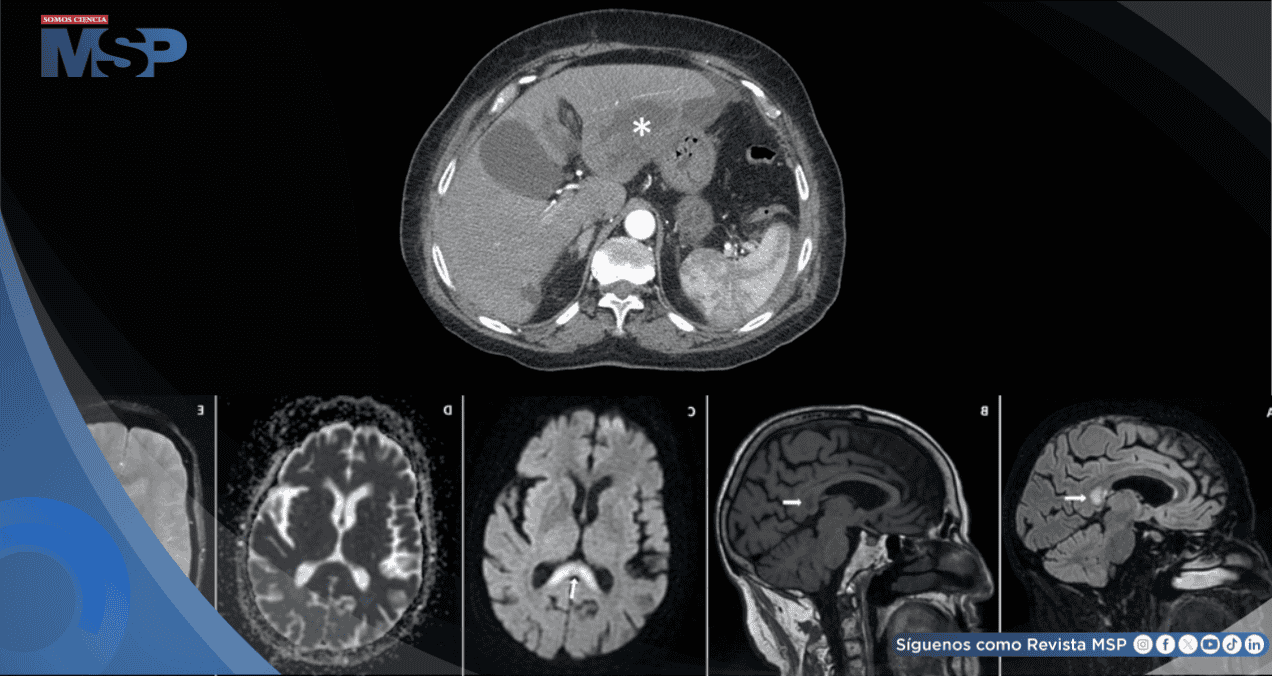

Una resonancia magnética cerebral realizada 10 días después de suspender el metronidazol proporcionó hallazgos objetivos que apoyaron el diagnóstico. La imagen mostró una lesión hiperintensa (que se ve brillante) en el esplenio del cuerpo calloso (una estructura que conecta los dos hemisferios cerebrales) en las secuencias T2 y T2-FLAIR. Esta lesión aparecía oscura (hipointensa) en las imágenes T1.

En las secuencias de difusión (DWI), la lesión también era hiperintensa, pero no mostraba restricción de la difusión en el mapa ADC, un patrón que puede verse en las encefalopatías tóxico-metabólicas. No se observaron signos de hemorragia. Estos hallazgos son característicos, aunque no exclusivos, de la neurotoxicidad por metronidazol.